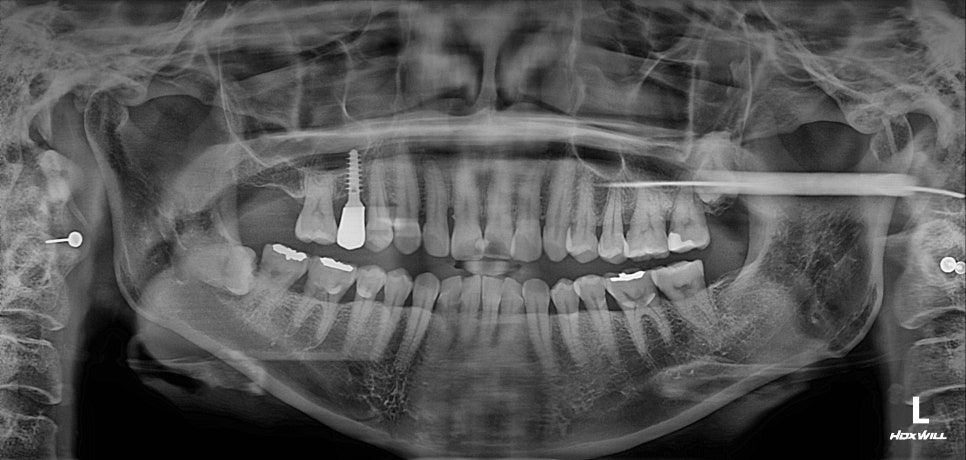

무절개 무봉합 상악동거상술

이용하여 발치자리에 있던 재생조직들도 살리고

통증, 붓기 감소는 물론

비용도 줄일 수 있었습니다.

실제 환자 입속에는 어떠한 절개부위나

꼬맨 흔적이 없답니다.

치료가 완벽하게 끝난 상태입니다.